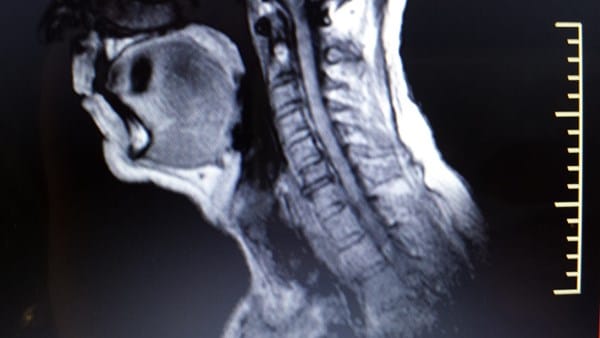

2/ Resonancia Magnética

Donde aparece espondiloartrosis con esclerosis de plataformas vertebrales y bordes ostofiticos

Osteartrosis en las articulaciones unciformes e interapofisiarias posteriores.

Discatrosis con baja señal de intensidad discal en secuencia T2

A nivel C3-4 Abombamiento discal paracentral y foraminal izquierdo

A nivel C4-5 Abombamiento discal con leve compromiso bilateral

A nivel C5-C6-C7 importantes abombamientos discales con compromiso bilateral-

Adjunto fotografias de la resonancia.